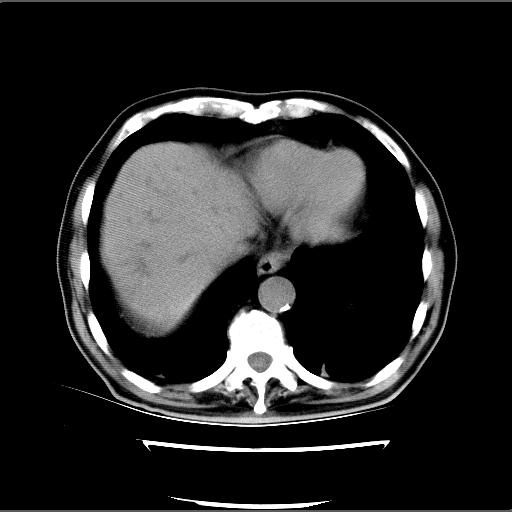

患者男82岁,黄染,发热10天,无腹痛。

1胆总管下端结石伴肝内外胆管扩张;2胆囊颈部结石伴胆囊积液

胆囊多发结石,胆囊积液;胆总管中下段结石,中上段扩张。

胆总管下段结石伴胆道系统扩张;胆囊炎伴胆囊结石.

此病例有结果了:患者术后为:胆总管下段结石伴胆道系统扩张;胆囊炎伴胆囊结石。

各位战友分析的都很正确,是一个典型的病例。